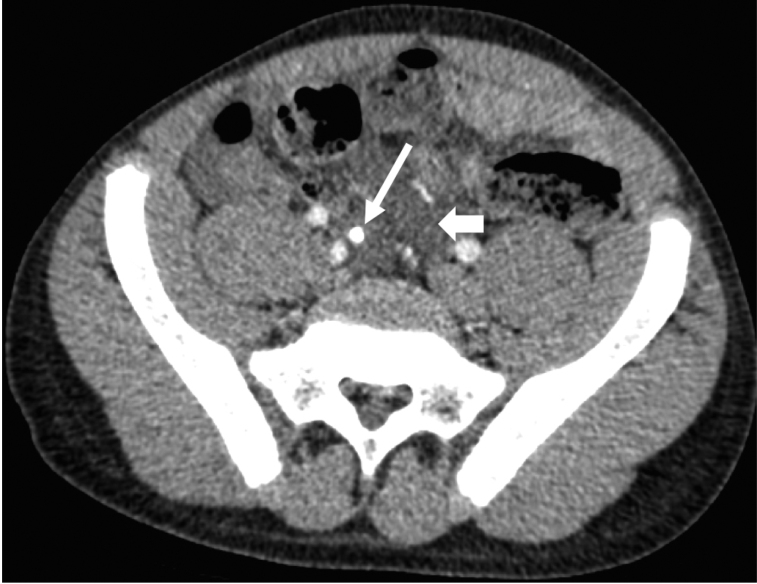

CT studies showed the presence of inflammatory changes in the RIF, with fat-stranding, enlarged mesenteric lymph nodes and free fluid. One patient had a markedly thickened caecum and adjacent terminal ileum, with extensive inflammatory change making it extremely difficult to delineate the appendix (Figure 2). Small-bowel intussusception was noted in one patient, associated with small bowel wall thickening. Two patients did not undergo imaging.

Figure 2 .

CT abdomen in a 14-year-old male with sepsis: marked caecal wall thickening (thin arrow) surrounded by mesenteric hazy fat-stranding (thick arrows). There was also a small amount of free fluid and local lymphadenopathy (not shown here). The appendix could not be identified due to the marked inflammatory change. CT = Computed Tomography.